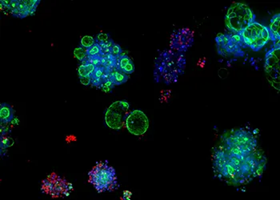

Colorectal cancer (CRC) organoids

Image Credit: Molecular Devices UK Ltd

Ten CRC organoid (PDO) lines have been developed using adult stem cells from colorectal cancer patient biopsy tissue.

Colorectal cancer (CRC) organoids

Image Credit: Molecular Devices UK Ltd

Patient-derived colorectal cancer organoids, also known as colorectal cancer PDOs or CRC organoids, are multicellular miniature versions of the three-dimensional tumor that are cultivated in a laboratory. It has been demonstrated that they exhibit drug responses comparable to those of their derived organoids and maintain the in vivo features of the original tumor. This presents revolutionary opportunities for drug discovery and medical research.